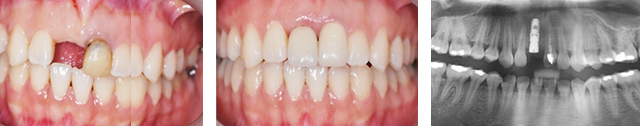

앞니 상실과 보철물 오염으로 내원한 환자분. 오른쪽 오염된 보철물로 인하여 잇몸이 올라간 상태, 치주치료와 올세라믹 치료를 하고 상실된 부위에 임플란트를 식립 하였습니다. 앞니의 경우 외모를 결정시키는 중요한 의미가 있기 때문에 자연치아와 구별 안될 정도로 자연스럽게 만들어 드렸습니다.